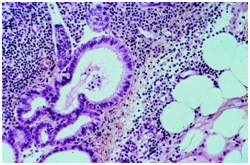

- Mullerian type epithelium: Glandular inclusions inter-lined by cuboidal cells simulating a mullerian or coelomic epithelium may be located in the pelvic lymph nodes. The inclusions may resemble the peritoneal lesions denominated as “endosalpingosis”. Metastasis from a low grade ovarian neoplasm which may extend in the peripheral sinus, lesions which form papillae, the emergence of psammoma bodies or cellular proliferations configuring small, laminated layers are the conditions which require a distinction from the inclusions of mullerian type epithelium. Nodal endometriosis may accompany the glandular inclusions with an encompassing endometrial type stroma.5

Figure 4 Cystic mullerian duct inclusions in the lymph node